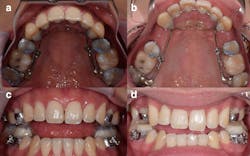

What she said happened next was ghastly. Kragulj alleged in her lawsuit that instead of changing her jaw, the device pushed her teeth forward through the bone that anchors their roots in place, which put her front teeth in jeopardy. Dozens of photos provided by her attorney show that over time her teeth bulged out of her mouth, warping her smile into a twisted mess. In the three years since filing her suit, Kragulj has had four unsalvageable teeth removed and two others ground to nubs, she said.

Dentists across the country promote the AGGA on their websites, often claiming it can “grow,” “remodel,” or “expand” an adult’s jaw without surgery, sometimes saying it has the potential to make patients more attractive and treat common ailments like sleep apnea and TMJ. However, after reviewing dental scans that the AGGA inventor submitted in court to prove the device works, eight experts told KHN and CBS News the scans show signs of the AGGA displacing teeth instead of expanding the jaw. Some experts said, based on their experience with former AGGA patients, the device caused tens of thousands of dollars in damage to the patient’s mouths.

However, in a series of interviews with orthodontists, periodontists, and maxillofacial surgeons — all of whom have more training than the average dentist — these experts said that while it is possible to expand the jaws of children without surgery, jawbones stop growing forward as people mature into adulthood. Experts who have examined patients fitted with an AGGA said the device aggressively moved teeth, sometimes creating an illusion of jaw growth by tilting some teeth forward and forcing gaps between others. In the worst cases, those experts have seen teeth shoved so far out of position that their roots are pushed free of the bone and into the gums.

Dr. George Mandelaris, a Chicago-area periodontist and member of the American Academy of Periodontology Board of Trustees, said Galella’s dental scans show “harm” to the bone that holds teeth in place. Mandelaris said he has consulted with 11 AGGA patients, including Kragulj, who looked as if “a bomb went off in her mouth.”

Kragulj, the clarinetist from the beginning of this article, said she discovered the AGGA through a Facebook video from Galella’s Facial Beauty Institute. According to her lawsuit, she got a device in 2018 and wore it for about 14 months, by which point she had sustained “irreversible” damage to the bone that holds her teeth in place.

After the meeting, Kragulj decided she was done with Galella, according to her lawsuit. She said she returned to the traditional surgeons and specialists she once eschewed, and the first orthodontist she saw described her teeth as “the worst thing he’d ever seen.”

“They were hanging on by a thread, and the bone was gone,” Kragulj said in an interview. “So it was an extravagant process to get to a place where I could even have fake teeth.”

Kragulj said that since abandoning the AGGA treatment she had to remove four front teeth and was fitted with a dental bridge of false teeth. She said she will need surgery to fix the underlying problems in her jaw and will likely need to replace her upper teeth with prosthetics.